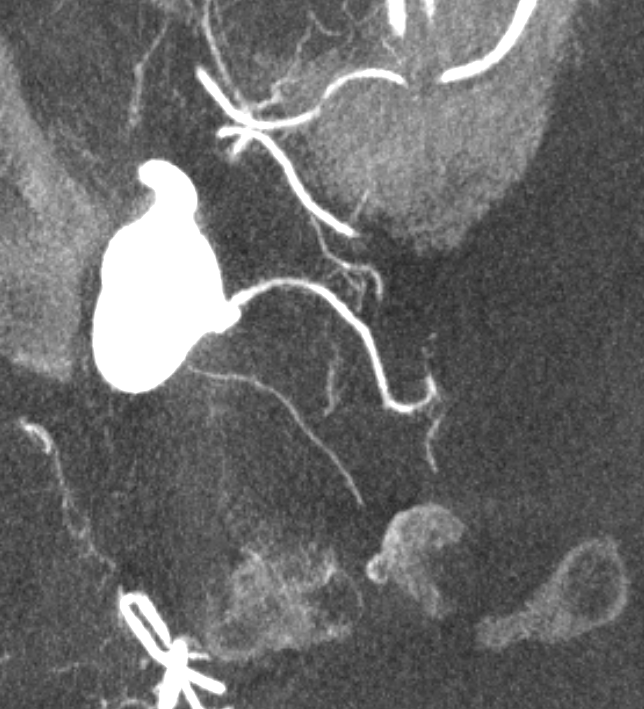

Capsular Arteries of McConnell

These are different from Superior Hypophyseals, but often come up together. This is because they were described by McConnell in a fantastic manuscript on arterial supply to the hypophysis. The anterior hypophysis is supplied by the aforementioned superior hypophyseals. Posterior by the inferior hypophyseals. The arteries of McConnell supply the dura and bone of the sella turcica. They are considered dural, and do not as a rule supply the hypophysis. Too small for even HR CBCT resolution, they are found in about 1/3 to 1/2 of surgical dissections. Origin is from the MEDIAL aspect of the horizontal cavernous segment (opposite side of ILT). Courses medially towards the bottom of the sella. Below (arrows) is a particularly large one (because it feeds some posterior pituitary for some reason). Note beautiful anterior pituitary / stalk supply on bottom right image.

Without arrows: